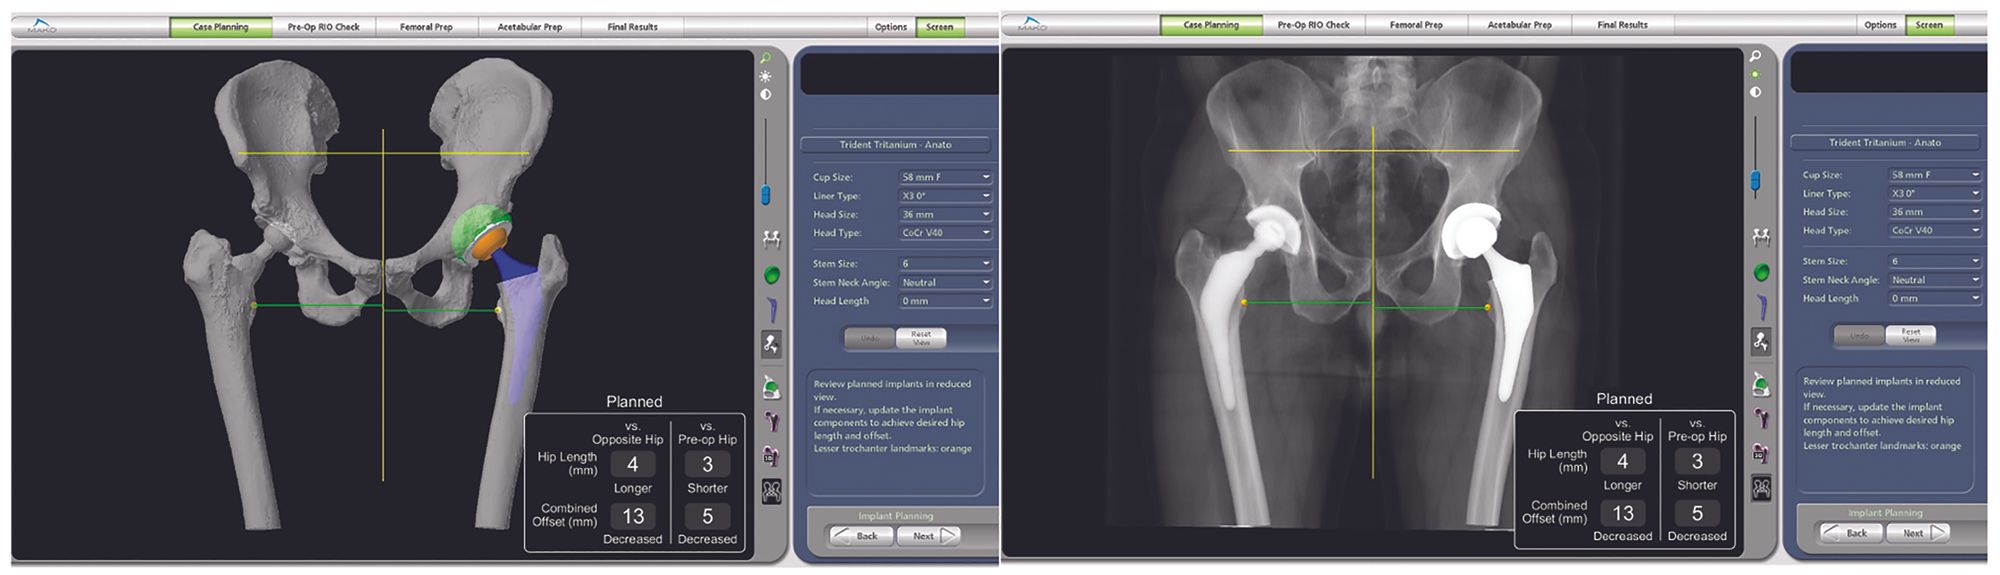

These choices are unpredictable and, in all cases, will depend entirely on the surgeon’s preferences when validating the final plan (Fig. 4), although changes may still be made mid-procedure based on findings or constraints.

Once the data have been reconciled, optimal reaming is ensured using the robotic arm with a single-size reamer positioned in accordance with the plan. This arm can restrict the surgeon’s movements in terms of orientation, centre of rotation and depth of reaming.

It also controls the final cup impaction. Using the probe to check final cup orientation ensures that the intraoperative values never differ from the plan by more than 2° (Fig. 6).

Once the femur is prepared, stem version, lateral shift and leg length data are collected from either the trial components or the final implant and may be used to make adjustments in head length by editing the plan and checking the data using intraoperative data acquisition.

The robotic system therefore means everything is double-checked during the procedure, once by the surgeon and once by the robot.